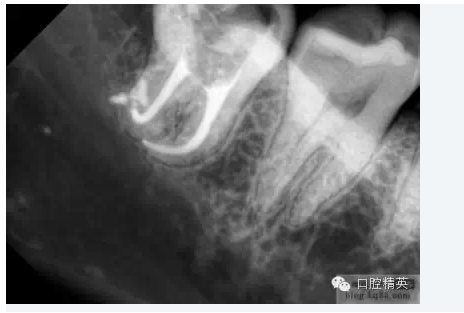

根尖1/3的擴(kuò)大及最后完成

當(dāng)根管的髓腔向2/3的擴(kuò)大完成以后,臨床牙醫(yī)即可順利的進(jìn)行根尖1/3的擴(kuò)大及最后精細(xì)完成。因?yàn)榇蟛糠值难栏鶑澢胺植娑及l(fā)生在該區(qū)域,所以,應(yīng)先應(yīng)用小型的不銹鋼可彎曲的根管擴(kuò)大針對(duì)其進(jìn)行小心而精密的探測(cè),以獲得更詳細(xì)而準(zhǔn)確的診斷資料。

1.根尖孔部位的預(yù)備小型的擴(kuò)孔銼能為我們提供關(guān)于根管尖端1/3解剖結(jié)構(gòu)的準(zhǔn)確信息,預(yù)先擴(kuò)大的根管髓腔側(cè)2/3可以保證經(jīng)過(guò)預(yù)彎的小型擴(kuò)孔器械自由出入,從而獲得關(guān)于根管尖端1/3解剖結(jié)構(gòu)的更明確的結(jié)論。正常情況下,根管系統(tǒng)會(huì)有一些根分叉、融合、彎曲等變異現(xiàn)象,甚至在同一部位同時(shí)出現(xiàn)幾種變異,此時(shí)對(duì)操作的要求就更高了。

2.確定根尖孔的合適開(kāi)放根據(jù)X線片(RT)確定的根尖孔位置,將一柔軟的10號(hào)擴(kuò)孔銼輕輕推進(jìn)。為了保證根尖孔的良好開(kāi)放,應(yīng)保證擴(kuò)孔銼尖端超過(guò)根尖孔1mm, 同時(shí)減少齲壞牙本質(zhì)碎霄的堆積 (在10號(hào)擴(kuò)孔銼其D1位置的直徑為0.12mm) ,輕輕的將之向前推進(jìn)1mm,以提供更大的空間,保證所有牙髓組織碎片、齲壞牙本質(zhì)碎霄的清除及沖洗液的自如進(jìn)出,同時(shí)降低根管堵塞的發(fā)生率。根尖孔完全開(kāi)放或10號(hào)擴(kuò)孔銼向前推進(jìn)幅度不足1mm都是不可取的,因?yàn)榕R床研究表明:兩種選擇的治療結(jié)果都不甚理想。

3.工作長(zhǎng)度經(jīng)驗(yàn)豐富的臨床牙醫(yī)可以根據(jù)以往經(jīng)驗(yàn)來(lái)判斷根管的工作長(zhǎng)度。作為輔助手段,電子根尖定位器能提供更準(zhǔn)確、更可信、更有價(jià)值的工作長(zhǎng)度信息,甚至在根管鈣化明顯或彎曲嚴(yán)重的病例也能對(duì)根尖孔進(jìn)行準(zhǔn)確定位。在操作過(guò)程中,切記一點(diǎn),電子根尖定位器只能作為X片的輔助手段,而不可完全代替?zhèn)鹘y(tǒng)X片的作用。當(dāng)根據(jù)X線片(RT)及電子根尖定位器,根管的工作長(zhǎng)度都已得到準(zhǔn)確確定后,即可采取多種方法對(duì)根管的根尖側(cè)1/3進(jìn)行最后的擴(kuò)大完成。